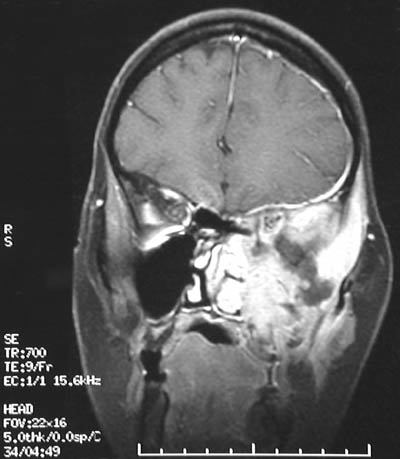

In coronal view, this T2 weighted MRI scan of the head of an adult shows a large infiltrative rhabdomyosarcoma arising in the left maxillary-pterygoid region.